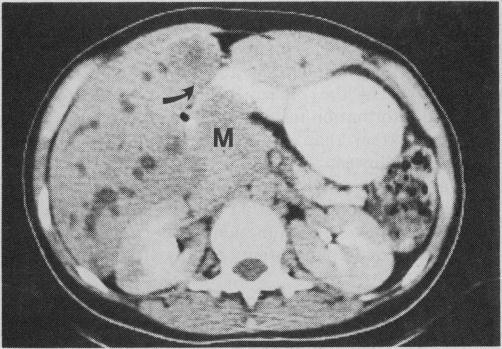

Data for 94 patients clinically suspected of having extrahepatic biliary obstruction who were referred for radiologic investigations were studied to compare the value of various imaging modalities used to detect this condition. Computed tomography emerged as the best indirect, noninvasive technique and percutaneous transhepatic cholangiography as the best direct technique. A standard approach to investigating suspected extrahepatic biliary obstruction is suggested that takes into consideration the interventional radiologic techniques currently used to treat this condition.

Radiologic investigation of suspected extrahepatic biliary obstruction.